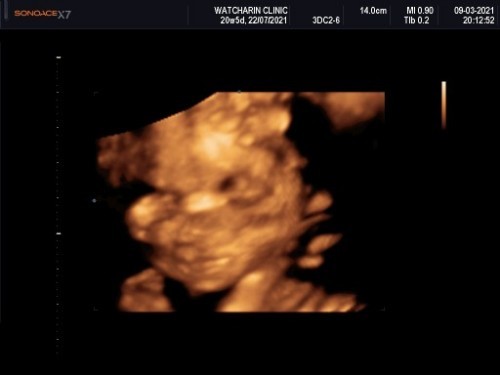

แม่ๆคนไหนซาวด์ 4มิติ แล้วลูกออกมาเหมือนใบซาวด์มั่งคะ บ้านนี้ท้อง3แล้วยังตื่นเต้นอยู่เลยคะ ผู้หญิง ทีม ก.ค คะ

นี่ก็ท้อง3เหมือนกันค่ะ..แต่ก็ยังตื่นเต้นเหมือนลูกคนแรกเลย..ทีมเมษาค่ะ